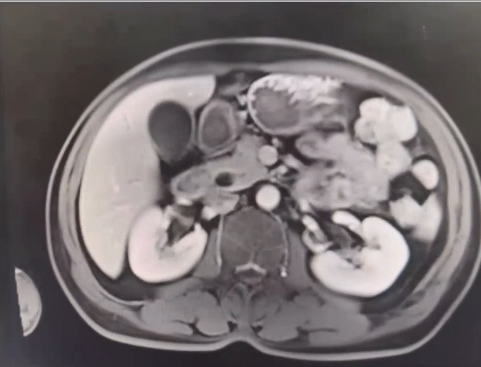

患者為57歲男性,近日就診于河北醫(yī)科大學第四醫(yī)院肝膽外科,入院后核磁檢查顯示十二指腸乳頭區(qū)軟組織信號腫物,考慮壺腹周圍癌可能,伴肝內外膽管擴張。壺腹部癌是生長在乏特壺腹、十二指腸乳頭、膽總管下端、胰管開口處、十二指腸內側壁癌的總稱,因腫瘤梗阻了膽總管和主胰管,通常會引起黃疸、膽囊腫大等。胰十二指腸切除術是治療胰頭及壺腹周圍腫瘤最為有效的外科術式,然而,該手術操作復雜,以“切除范圍大、吻合部位多、手術風險高”而著稱,被稱為腹部外科手術中的“珠穆朗瑪峰”。

▲病患入院影像檢查 - 靜脈期